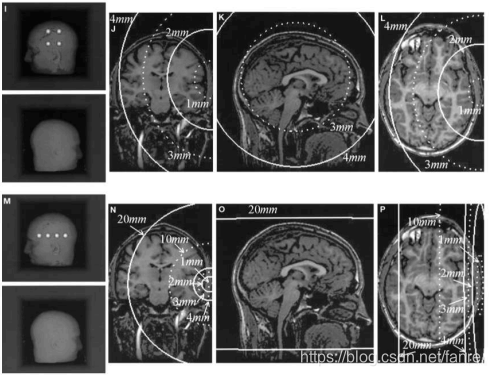

FRE:Fiducial Registration Error配准误差基准 -配准后对应基准点之间的均方根距离

FLE:Fiducial Localisation Error定位误差基准 -定位基准点的误差

TRE:Target Registration Error配准误差目标-除了基准点以外,对应点之间的距离,这是最重要的

随着目标与基准形心的距离增加,TRE值也增加

FRE不是一个可靠的配准准确性指标(!!)

- FRE独立于基准配置。

- FRE与偏置误差无关(如MRI梯度、数字化仪相机失调、手持探头弯曲)。

- TRE近似有

的相关性

:均方基准配准误差

:目标点到基准配置原理轴k的距离(平方)

:基准点与基准配置原则轴k之间的RMS(平方)。

对于基于学习的图像注册,注意事项仍然有效